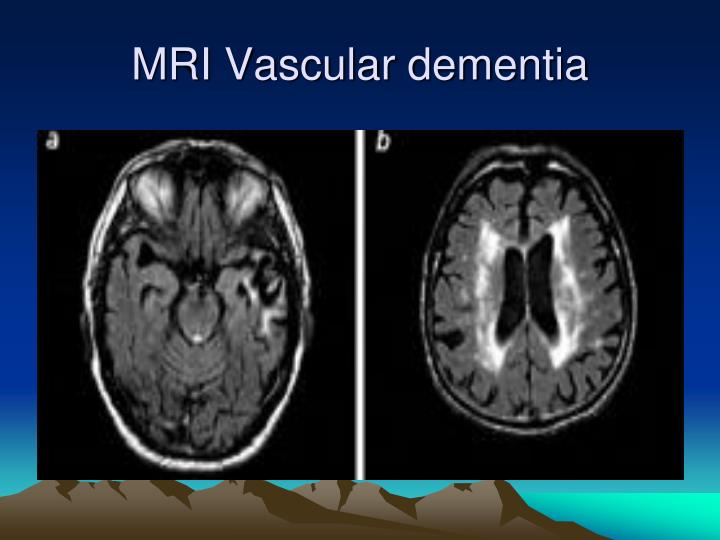

PPT - Dementia PowerPoint Presentation - ID:6714978

www.slideserve.com

www.slideserve.com

dementia mri vascular ppt presentation powerpoint slideserve disease

Vascular Dementia | Radiology Reference Article | Radiopaedia.org

radiopaedia.org

radiopaedia.org